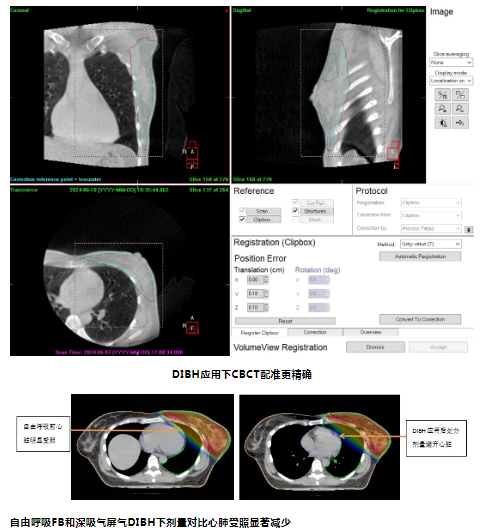

约70%肺癌、乳腺癌等肿瘤患者需要接受放射治疗,但胸部放疗同时会损伤心、肺等重要器官,降低心肺等器官的照射量是改善胸部放疗患者生活质量的关键。为此,放疗机房江丹贤主任,袁戈、吴成省、黄光森等科室骨干在广东医科大学附属医院一专科“一年一突破”战略的指引下,针对呼吸运动引起的内脏运动会导致正常组织照射增加的情况,于2024年6月17日成功开展基于光学体表监测的深吸气屏气放疗技术(DIBH)。

该例患者为乳腺癌保乳术后放疗,经应用深吸气屏气放疗技术后,深吸气使心脏与照射区域的距离拉开,且全肺体积比自然呼吸增加了29%,在保证靶区剂量充足的前提下显著降低了心脏及患侧肺的平均受照剂量,实现乳腺癌患者放疗的高效低毒。